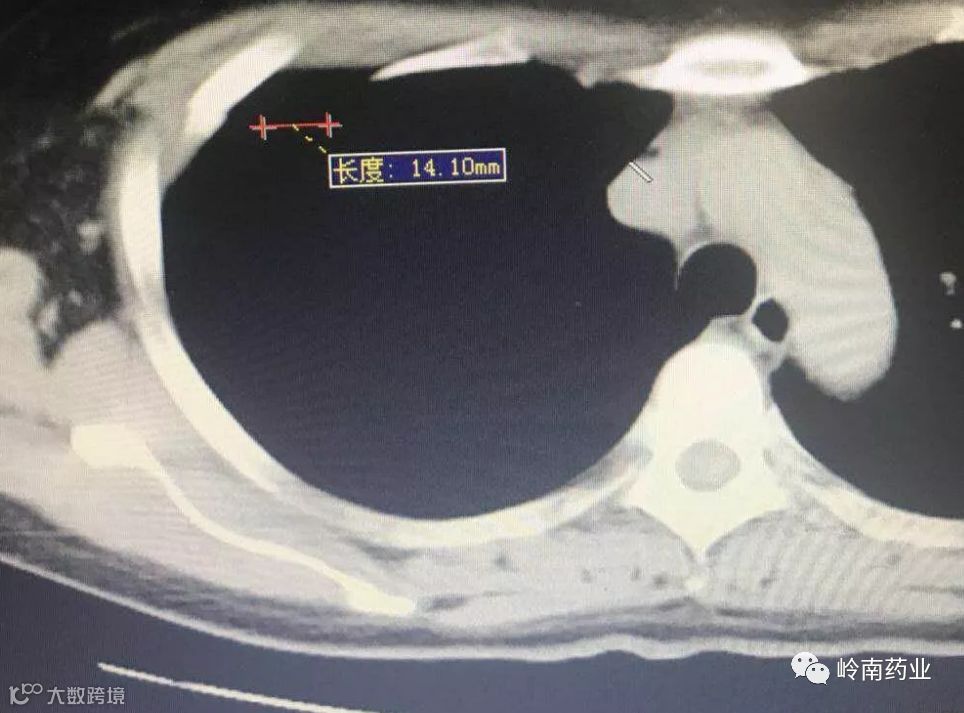

4月22日,王女士在家人的陪伴下到医院胸外科就诊,经过X光胸片检查,发现她的胸肋骨骨折错位非常明显,胸部疼痛不适与第3、4、5、6、7五根胸肋骨骨折有关。